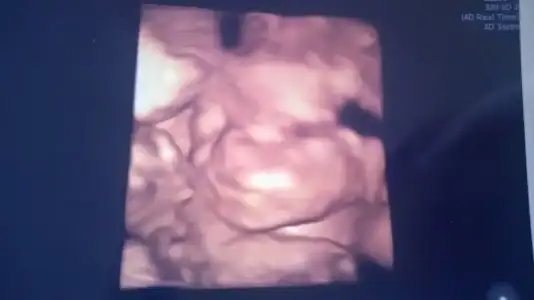

Kızlar günaydın ... Senelik izindeyim biraz işler vardı koşturmaktan giremedim forma herkes iyi demi :) okumadığım bikaç sayfa var onlarıda okuycam inş. Gün içinde ben dun detaylı ultrsona girdim herşey şukur yolunda kızım gayet sağlıklıymış biraz utangaç yuzunu azıcık gösterdi ...yinede doktor bir poz yakaladı işte Lidya teyzeleri

Eklentiler

• WP_20150818_002.webp

WP_20150818_002.webp

9,6 KB · Görüntüleme: 86